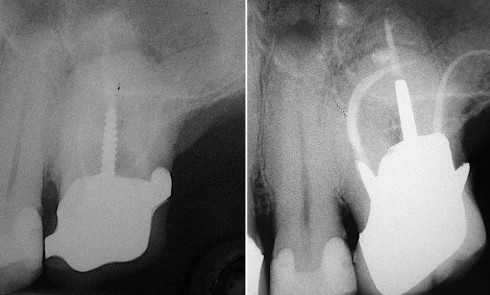

La compréhension de ces instruments, des biomatériaux et des différentes techniques est essentielle, et doit nous guider dans nos prises de décision en fonction des situations cliniques. Dans le cas clinique présent, suivi sur 24 mois, le patient se présente avec des douleurs à la mastication sur la dent 36. Tous les signes cliniques (test au froid négatif, test à la percussion positif, sondage parodontal positif en vestibulo-distal avec présence de fistule) et les examens radiologiques (LIPOE sur la racine distale, lésion inter-radiculaire) convergent vers un diagnostic de nécrose pulpaire due à une fracture longitudinale non complète (type 3 : Classification AAD) [1] (fig. 1).

Lors du suivi clinique et radiologique à 24 mois, nous observons une cicatrisation de la LIPOE, et la dent est asymptomatique (fig. 11 et 12).